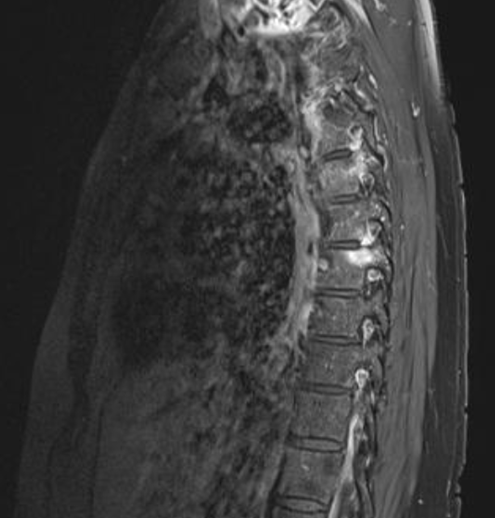

Zusätzlich klagte die Patientin über 7 schmerzende Gelenke (Tender Joint Count (TJC): 7). Die Schmerzen gab sie auf der Visuellen Analog Skala (VAS) mit 70 von 100 an. Besonders nachts waren die Rückenschmerzen quälend, während Bewegung tagsüber Linderung brachte. Die Blutsenkung lag bei 27 mm/h und der CRP-Wert bei 1,13 mg/dl. Rheumafaktor und CCP-AK waren nicht erhöht. Die Patientin war HLA-B27 negativ. Eine Untersuchung der Brustwirbelsäule im Februar 2020 zeigte eine Hyperämie am Kostotransversalgelenk und anteilig am Kostovertebralgelenk von BWK 7 links mit Ödem im angrenzenden Pedikel sowie diskrete Veränderungen auch an BWK 5 und eine diskale Enthesitis im Bereich BWK 5/6 rechts.

Abb. 1: MRT-Aufnahme vor der Therapie mit Taltz®